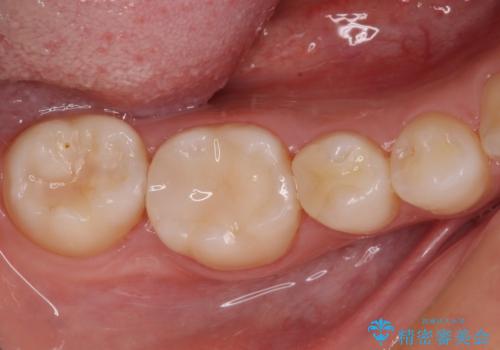

レントゲン写真などから、速やかに処置を行うべき歯が2歯あったため、それぞれセラミックインレーとPGAインレー(ゴールドインレー)にて修復治療を行うこととしました。

どちらの歯も痛みなどの症状はなく、治療後も異常所見なく経過をたどっています。

上顎大臼歯は向かい合った人から見えることはほとんどないため、切削量が少なく、適合の良いゴールドインレーが大変おすすめとなります。